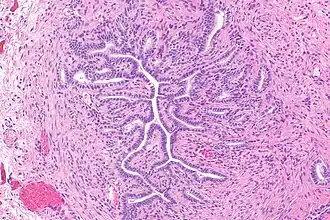

De gang van Gartner (ductus longitudinalis epoophori) is een gepaard, embryologisch overblijfsel tijdens de ontwikkeling van de gangen van Wolff bij de vorming van het urinewegstelsel en de voortplantingsorganen.[1] Het werd ontdekt en beschreven in 1822 door Hermann Treschow Gartner.

Als de gangen van Gartner voorkomen dan liggen ze aan de zijkanten in de brede moederbanden (ligamentum latum uteri) van de baarmoeder, de baarmoederhals en het bovenste deel van de vagina.

Tijdens de embryologische ontwikkeling verdwijnen de gangen van Wolff meestal helemaal. Maar ongeveer 25% van de volwassen vrouwen heeft overblijfselen van deze gangen, de gangen van Gartner. In sommige zeldzame gevallen kunnen cysten in deze gangen ontstaan.